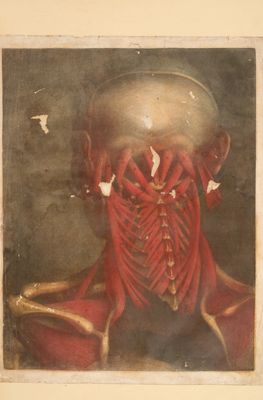

Myologie complette en couleur et grandeur naturelle, composée de l'Essai et de la Suite de l'Essai d'anatomie, en tableux imprimés [d'après les parties disséquées et préparées / par M. Duverney.

- Jacques Fabien Gautier d'Agoty

- 1746[-1748]

Credit: Myologie complette en couleur et grandeur naturelle, composée de l'Essai et de la Suite de l'Essai d'anatomie, en tableux imprimés [d'après les parties disséquées et préparées / par M. Duverney. Source: Wellcome Collection.